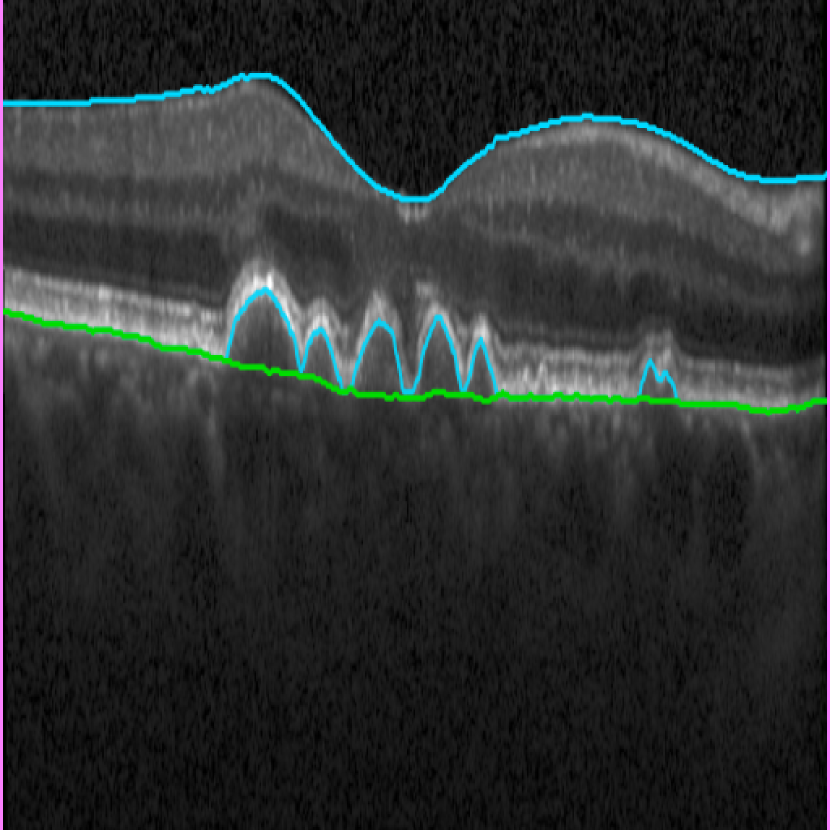

Bruch’s Membrane is an elastic smooth and thin structure, strategically located between the retina and the general circulation, having a crucial role in retinal function, aging and disease [14]. Automated segmentation of the BM is particularly important in the context of AMD as, unlike other common retinal diseases such as DR, RVO, or glaucoma, the BM is distinguishable from the outer RPE boundary. In specific, drusen in iAMD and PEDs in nAMD separate the RPE from BM, requiring the segmentation of the region in-between them. In addition, in case of GA, the RPE is completely lost in some locations, exposing only the BM, thus imposing additional difficulties for algorithms and calculations that depend on the RPE position. Achieving correct automated identification of the BM is challenging in many cases, mainly due to the small thickness of this layer, the high reflectivity of the RPE that shadows parts of the BM, and the noise being present in the scans, which is often indistinguishable from the content of drusen and PEDs (Fig. 4). Due to these difficulties, currently many automated solutions either do not provide a segmentation of the BM or its segmentation is often inaccurate in retinal OCT with AMD, leaving this clinically relevant segmentation task unaddressed or under-explored.

(a) iAMD

(b) nAMD

(c) GA